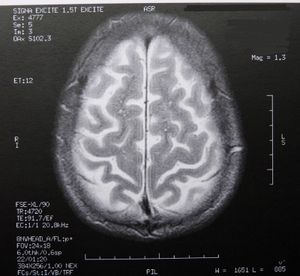

MRT: Unmenge an neuen Daten über das Gehirn. Bild: pixelio.de, Dieter Schütz